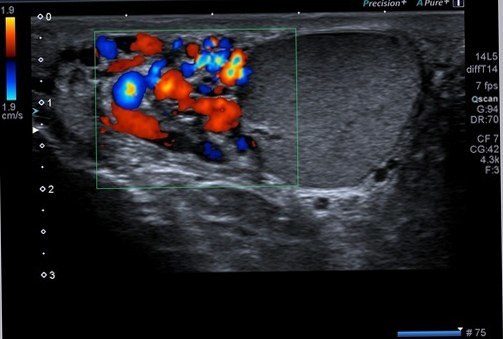

Varikosel için renkli doppler ultrasonu incelemesi de gerekecektir.

Şekilde testis komşuluğundaki yuvarlak siyah görünümde genişlemiş toplar damarlar ( varikosel) görülmektedir.